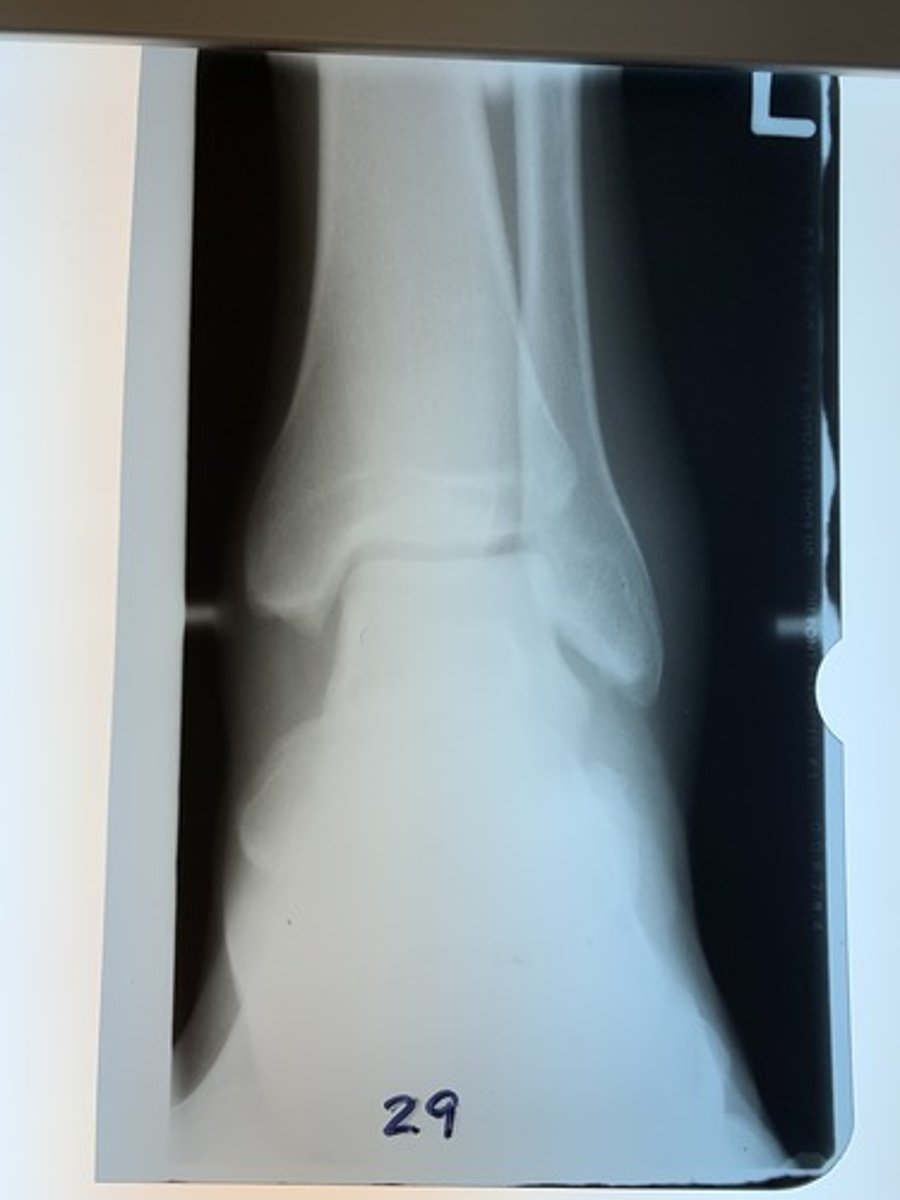

Is radiograph 29 acceptable, underexposed (inadequate mAs), or under-penetrated (inadequate kVp)?

Underexposed